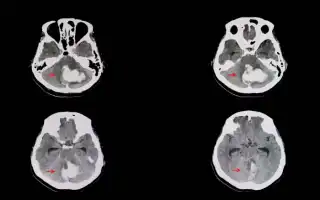

Инсульт, при котором происходит поражение мозжечковых отделов головного мозга возникает в результате двух негативных факторов – при сокращении либо полном прерывании подачи артериальной крови в эту область или при внутримозговом кровоизлиянии, поражающем этот орган. Соответственно медики могут различать ишемический инсульт мозжечка (возникающий в первом случае, при недостатке артериальной крови) и геморрагическую его форму (как во втором, при кровоизлиянии).

Ишемического типа мозжечковый инсульт развивается чаще нежели церебральная патология геморрагического типа и бывает обусловлен: спазмом, атеросклерозом, тромбозом сосудов, резким скачком артериального давления. Результатом уменьшения притока артериальной крови к мозжечковым отделам является некроз мозговых тканей, что собственно и ведет к утрате вышеописанных функций.

Геморрагического типа инсульт, чаще всего, наступает из-за разрыва или повышенной проницаемости кровеносных сосудов. А поскольку такой отдел головного мозга как мозжечок имеет довольно малые размеры, то для развития мозжечковой инсульт-патологии достаточно даже самого минимального капиллярного кровоизлияния. Последствия геморрагического поражения мозжечковых отделов всегда более опасны, в особенности, если проблема обусловлена разрывом аневризмы сосудов, что сопровождается обширным кровоизлиянием.